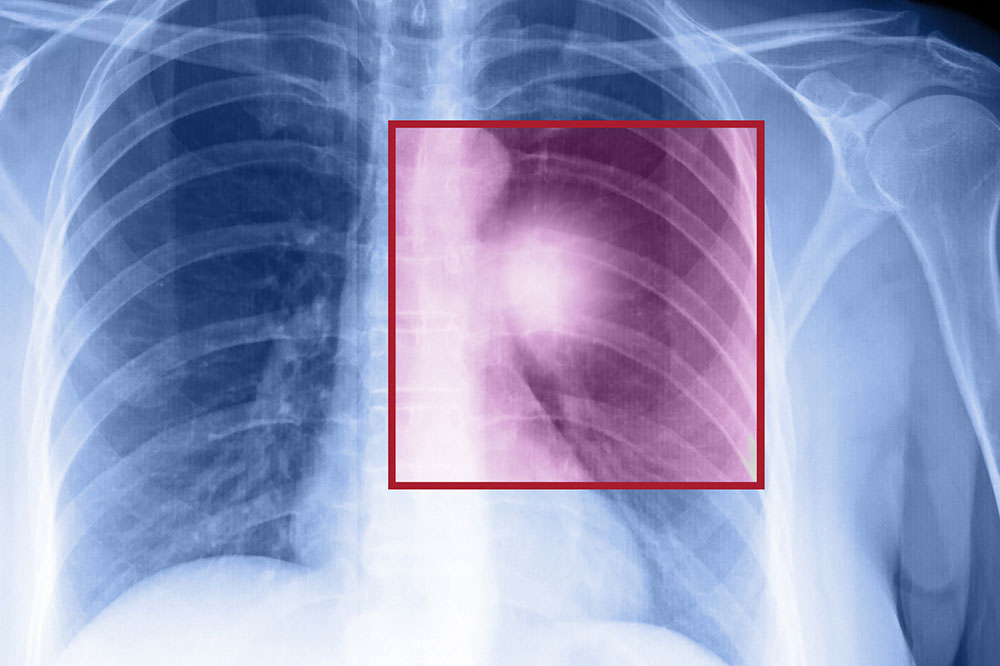

When the cells in the lungs begin to abnormally multiply and grow, it results in cancer. Lung cancer is one of the leading causes of death in the world. And the risk of suffering from this life-threatening disease is even higher when one is a smoker. Herein, we discuss the various factors that come into play when it comes to lung cancer.